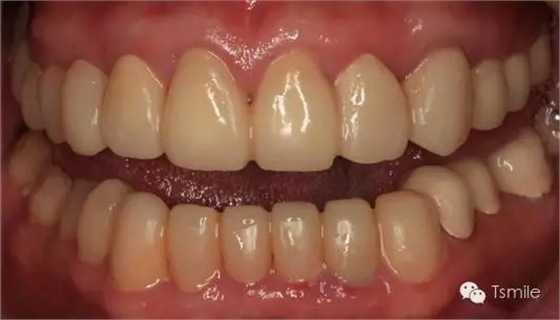

圖6:最終修復(fù)體完成 來源于tsmlie

前兩個美學(xué)分析和美學(xué)表達(dá)過程已經(jīng)確定了患者滿意的最終的美學(xué)修復(fù)設(shè)計,也就是已經(jīng)確定了最終修復(fù)體的形態(tài)、大小、排列、牙齦曲線等各種美學(xué)參數(shù),美學(xué)實(shí)現(xiàn)就是復(fù)制前面已經(jīng)確定的美學(xué)設(shè)計的過程,包括牙體預(yù)備、印模制取、修復(fù)體制作、修復(fù)體試戴粘接等過程。